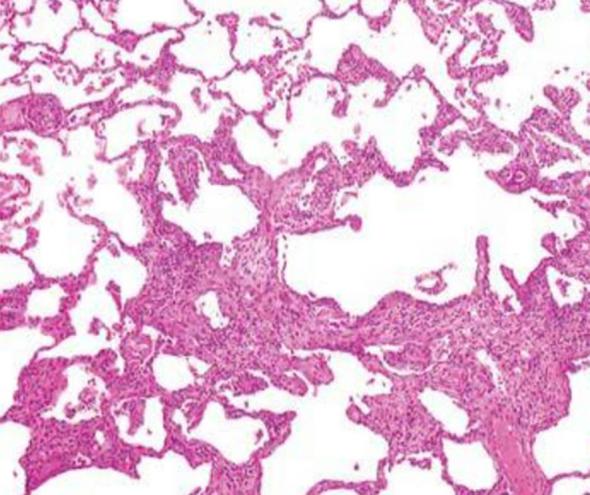

A 55-year-old Caucasian man, with a six-month medical history of UC under long-term maintenance treatment with oral mesalazine, presented with a week-long low-grade fever, dry cough and a diffuse bilateral centrilobular ill-defined micronodular pattern in chest imaging. On examination, he had dyspnea with hypoxemic respiratory failure. After extensive workup, potential differential diagnoses such as pulmonary infections were ruled out. Bronchoalveolar lavage (BAL) cellular analysis demonstrated a predominance of lymphocytes and an eosinophilia. The transbronchial biopsy findings confirmed lymphocytic alveolitis. The diagnosis of subacute HP was made with confidence because of the compatible clinical, radiographic, physiologic, BAL and histopathologic findings. Mesalazine withdrawal was decided. Substantial clinical improvement was promptly noticed. The fever abated within 24 hours alongside with a significant improvement of arterial oxygen saturation and lung function parameters. A radiological recovery was also gradually noticed.

一名55岁的白人男性,有6个月的UC病史,长期口服美沙拉嗪进行维持治疗,出现了持续一周的低热、干咳,胸部影像学显示双侧弥漫性小叶中心性边界不清的微小结节影。检查时,他有呼吸困难伴低氧性呼吸衰竭。经过广泛检查,排除了肺部感染等潜在的鉴别诊断。支气管肺泡灌洗(BAL)细胞分析显示淋巴细胞占优势且有嗜酸性粒细胞增多。经支气管活检结果证实为淋巴细胞性肺泡炎。由于临床、影像学、生理学、BAL和组织病理学结果相符,确诊为亚急性HP。决定停用美沙拉嗪。很快就注意到临床有显著改善。发热在24小时内消退,同时动脉血氧饱和度和肺功能参数有明显改善。影像学上也逐渐恢复。